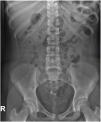

Presentamos el caso de una paciente de 14 años valorada en urgencias por dolor cólico en flanco derecho irradiado hacia hipogastrio. Se realizó una analítica de orina que fue normal, y dada la clínica compatible con cólico renal, una radiografía de abdomen (fig. 1).

Los tumores ováricos son raros en pediatría, representando entre el 1-5% de los tumores infantiles. Hasta el 90% de estos tumores son germinales, siendo el más frecuente el teratoma maduro (55-70% de las neoplasias ováricas en pediatría)1,2. El teratoma maduro ovárico es una entidad benigna que puede aparecer a cualquier edad, pero la prevalencia más alta se da en mujeres en la segunda y tercera década de la vida. Proviene de al menos 2 de las 3 capas de células germinales, siendo lo más habitual encontrar tejidos del ectodermo (pelo, grasa, dientes, piel…)2. La mayoría de las pacientes están asintomáticas al diagnóstico, encontrándose como un hallazgo casual en las pruebas de imagen, pero pueden presentar dolor abdominal, masa palpable en la exploración, complicaciones como la torsión o la rotura ovárica e incluso síndromes paraneoplásicos, aunque esta manifestación es muy rara. Hasta un 10% de los casos pediátricos pueden ser bilaterales3. El diagnóstico inicial se realiza mediante ecografía abdominal, siendo la imagen más común la de una lesión quística con un nódulo ecogénico compuesto de pelo, grasa o hueso, que suele presentar sombra acústica posterior (nódulo de Rokitansky). Habitualmente se completa el estudio con una resonancia magnética para delimitar mejor su tamaño y relación con estructuras vecinas2. Alrededor del 50% pueden tener calcificaciones y hasta en un 22% se pueden objetivar piezas dentarias radiológicamente4. Por ello, el hallazgo de imágenes con densidad calcio y forma de pieza dentaria en una radiografía de abdomen pueden ser clave en el diagnóstico de teratoma.